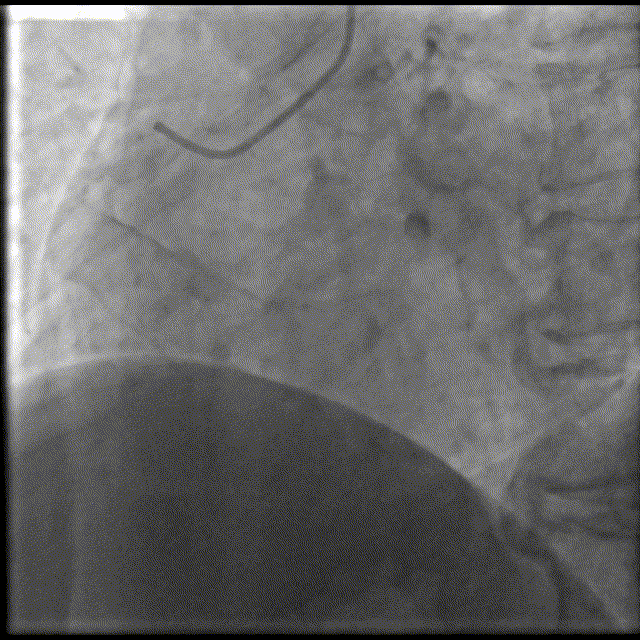

换用6F GC,Telescope™导引延长导管辅助下,2.5x15mm,14-16atm。

Telescope™导引延长导管辅助下,BAT技术,导引延长导管深达第二转折处,2.75x28mm支架顺利到位,12atm释放。

Telescope™导引延长导管辅助下,BAT技术,3.0x15mm,14-16atm后扩张。